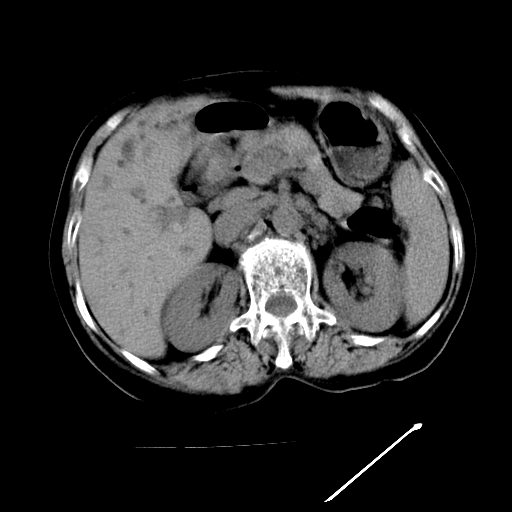

以下是引用随光逐影在2009-4-7 8:21:00的发言:[br]肝内外胆管多发性结石并肝内外胆管扩张;胆系感染。